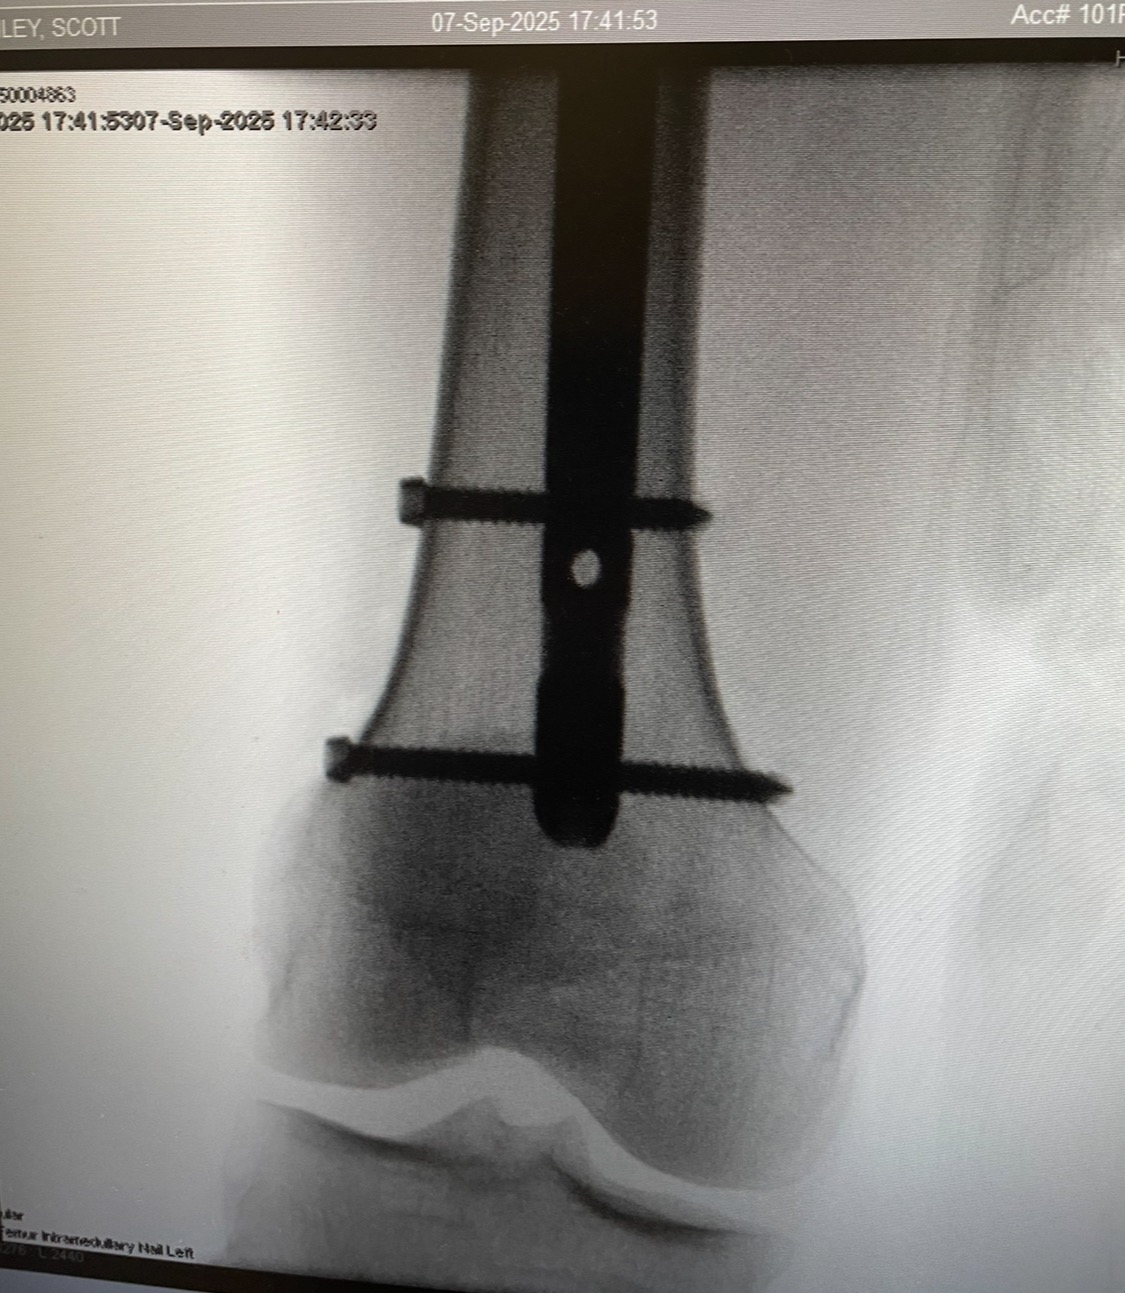

My name is Riley and on September 8, 2025, I suffered a significant injury—a fracture to my left femur—that has altered my life. On that morning while completing an errand near my home, a freak bail on my skateboard left my leg in dear condition. This injury requires extensive medical rehabilitation and a recovery period of 3 to 6 months, during which completing work is extremely difficult if at all possible. As a result, I am facing strenuous financial challenges without my regular ability to generate income, most notably my expenses for housing, food, and other necessary bills and debt payments.